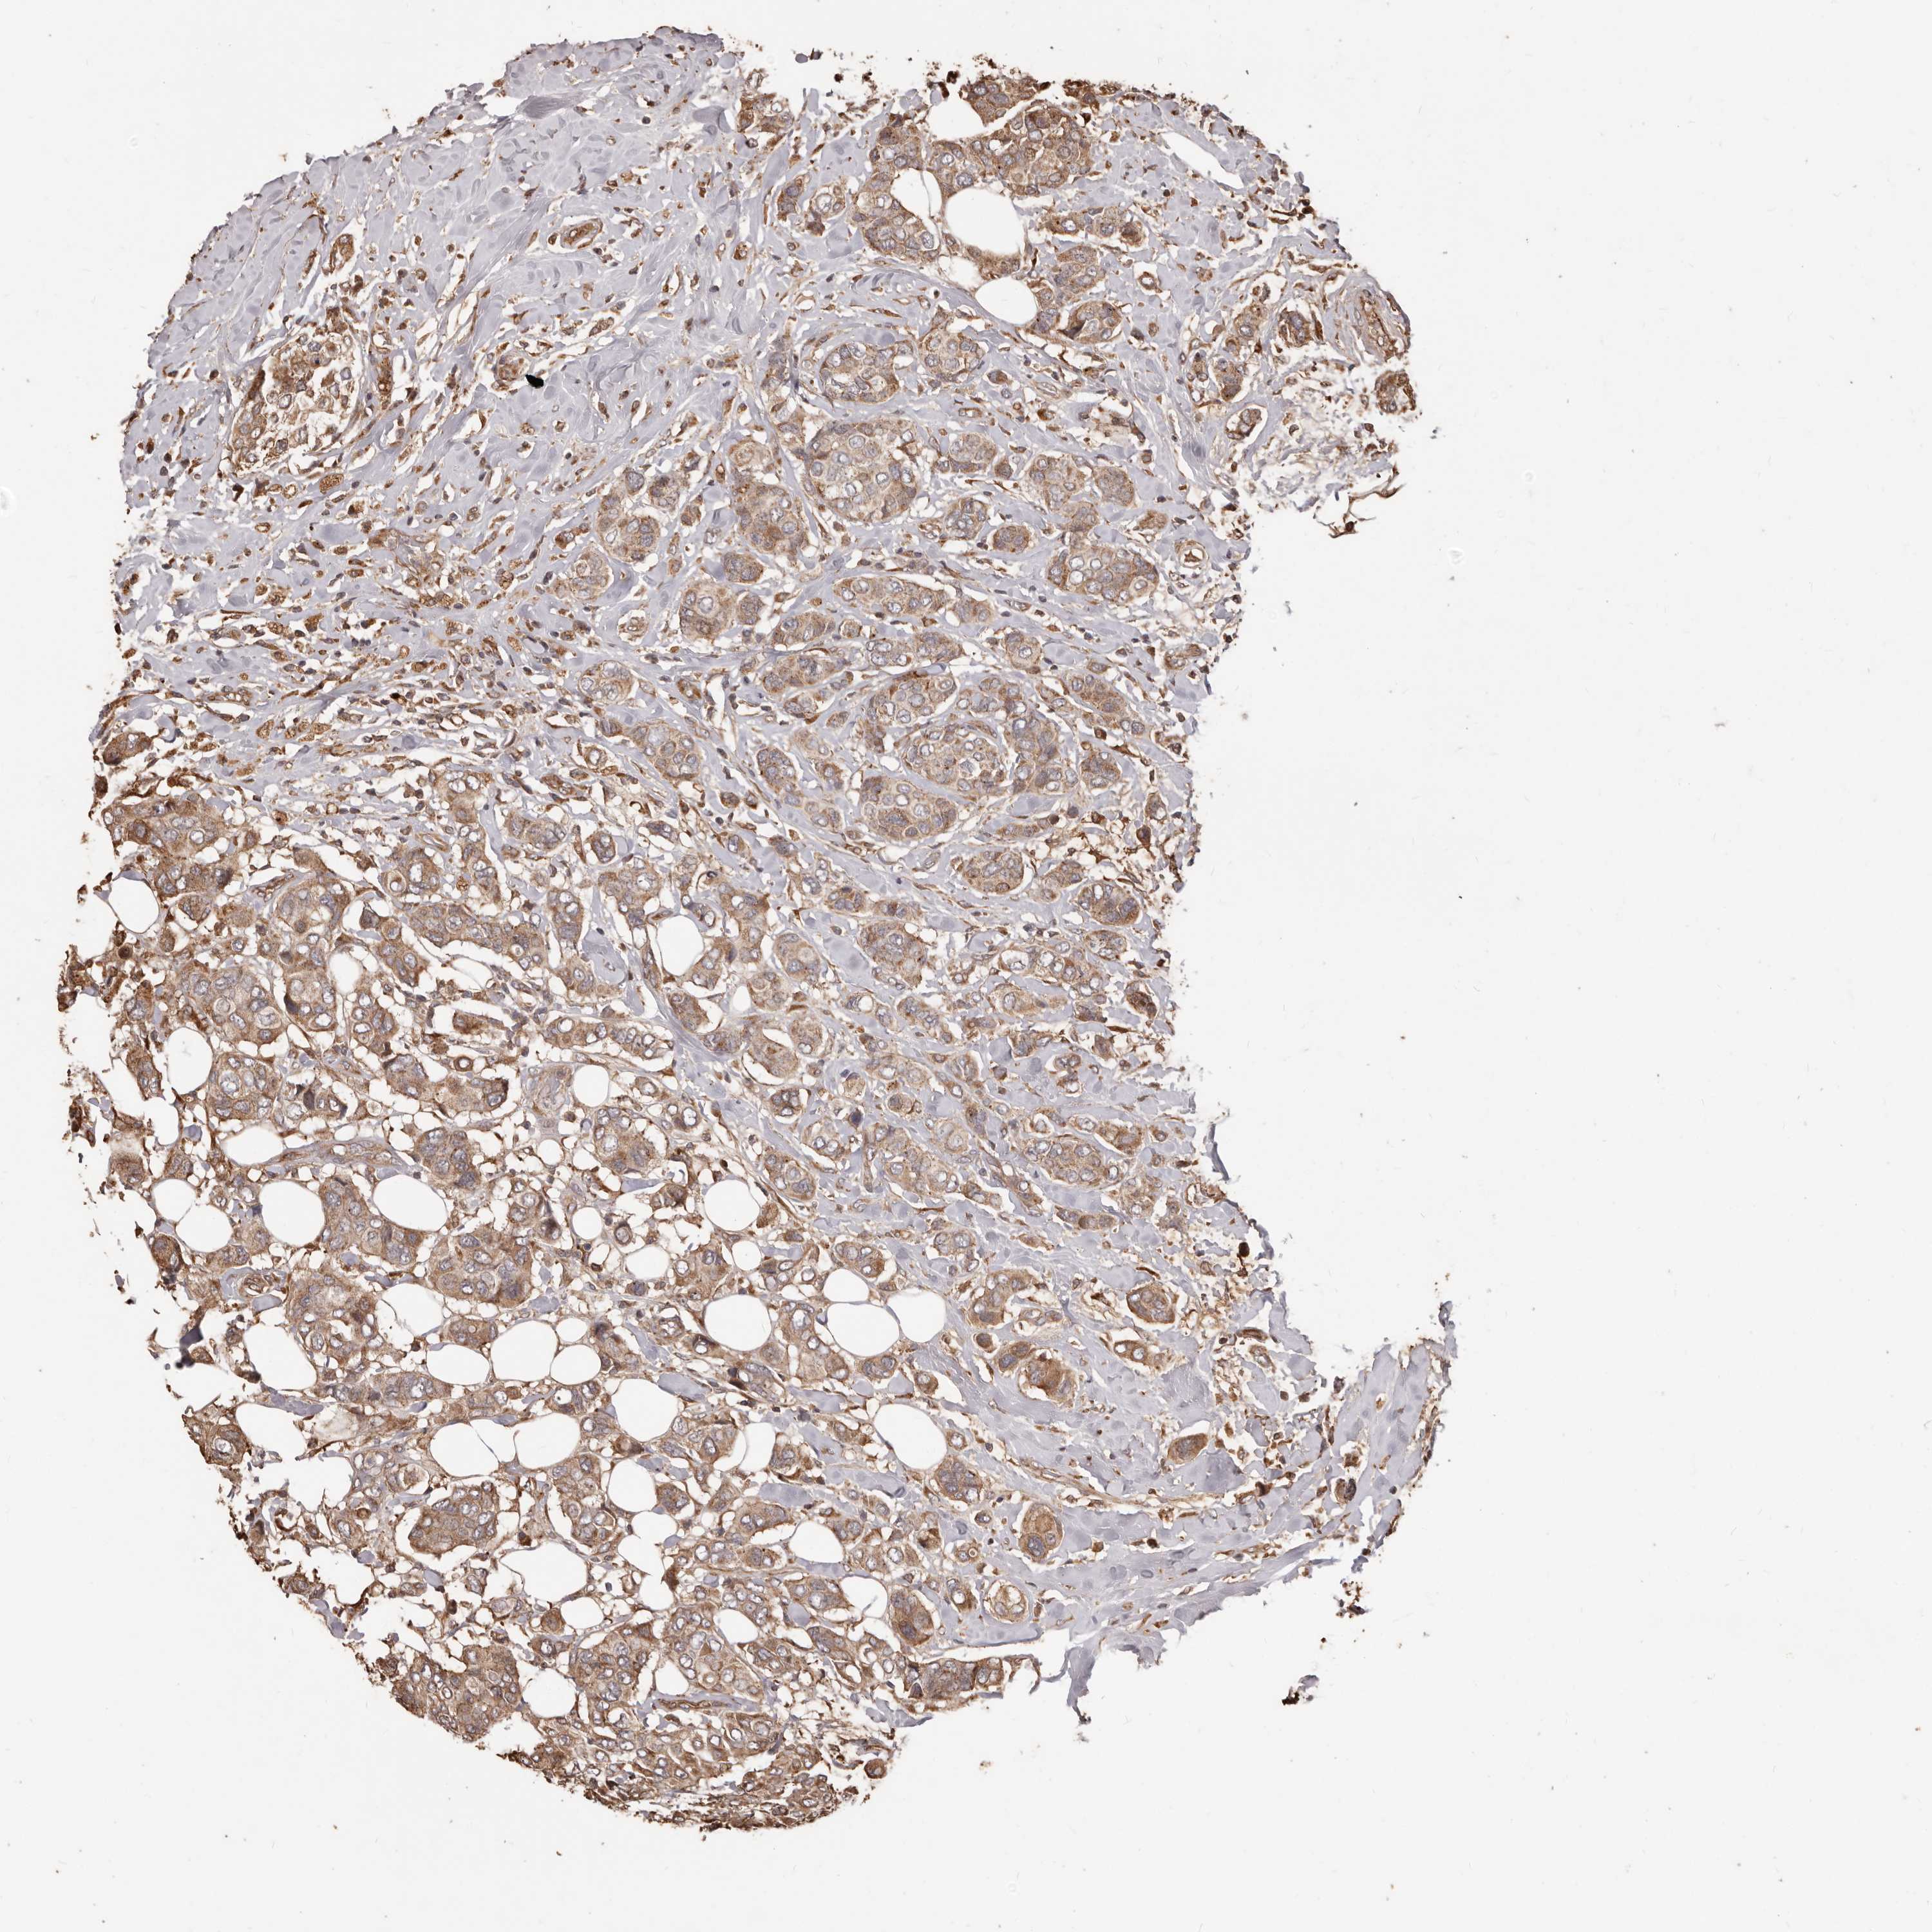

CANCER BREAST CANCER Show tissue menu

BRCA TCGA BRCA VALIDATION PROTEIN EXPRESSION

ANTIBODIES

AND

VALIDATION